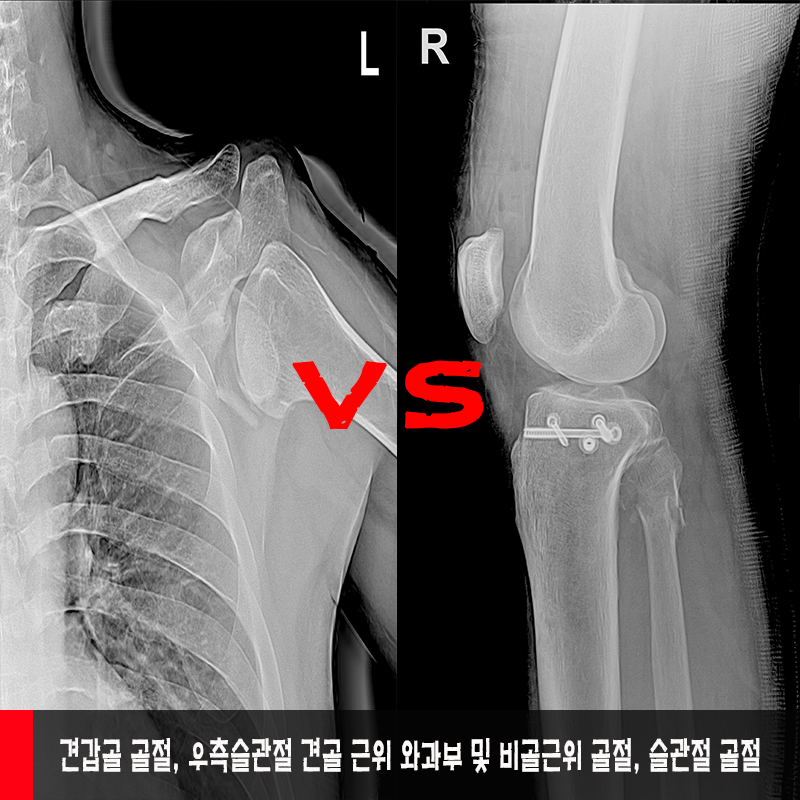

°ß°©°ñ °ñÀý, ¿ìÃø½½°üÀý °ß°ñ ±ÙÀ§

¿ÍºÎºÎ ¹× ºñ°ñ±ÙÀ§ °ñÀý, ½½°üÀý °ñÀý

¨è ¿ìÃø °ß°©°ñ üºÎ °ñÀý

°ß°©°ñ °ñÀý, ¿ìÃø½½°üÀý °ß°ñ